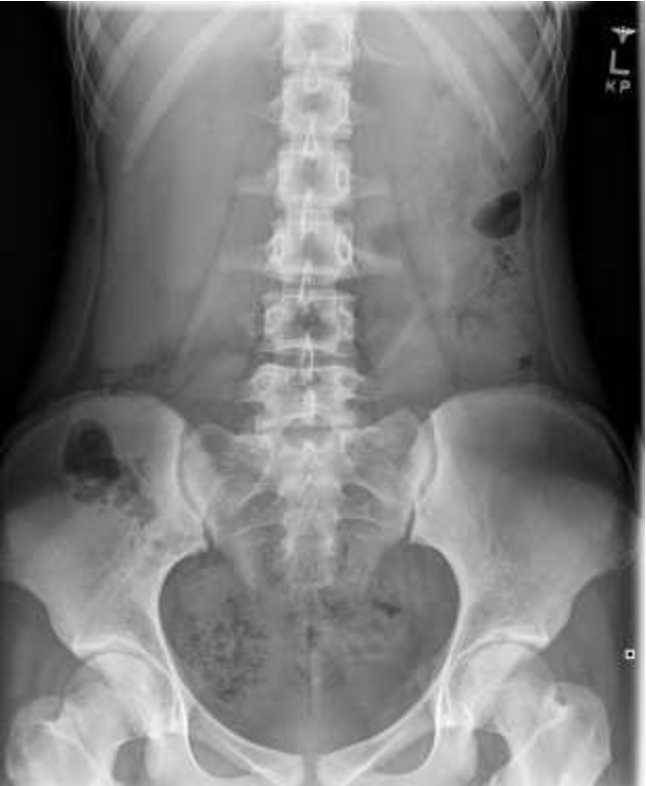

The diagnostic tests usually recommended for diagnosing Riedel’s Lobe are ultrasound, CT scan, MRI, and radionuclide imaging. The lesion is discovered with the hepatic ultrasound and vascular and cystic features can be depicted by the doppler test.